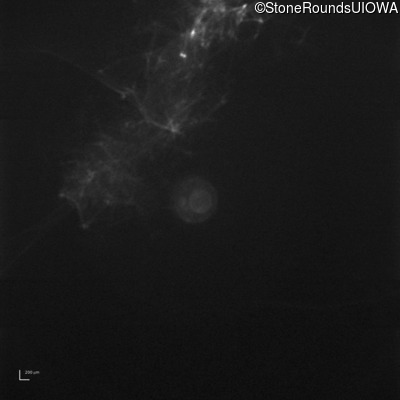

B-Scan Ultrasonography - Left - Light Perception Only

Exemplar